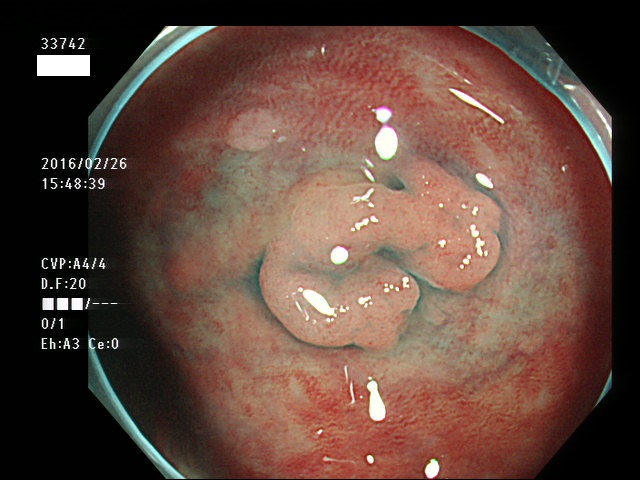

上記100名より抽出した平坦・陥凹型腺腫(=癌化の危険が高いが見落としやすい病変)の内視鏡写真